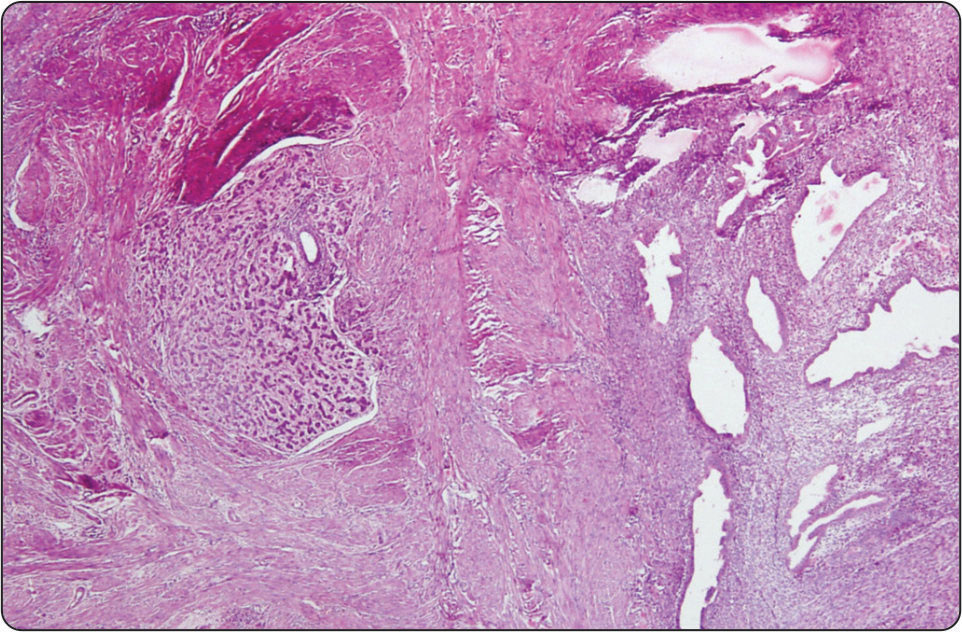

Plexiform Tumorlets of Uterus: A Case Report

Ujjawal Khurana, Gunjan Raghubanshi, Sunita Arora, RPS Punia, Harsh Mohan

page 48-50

Full text PDF